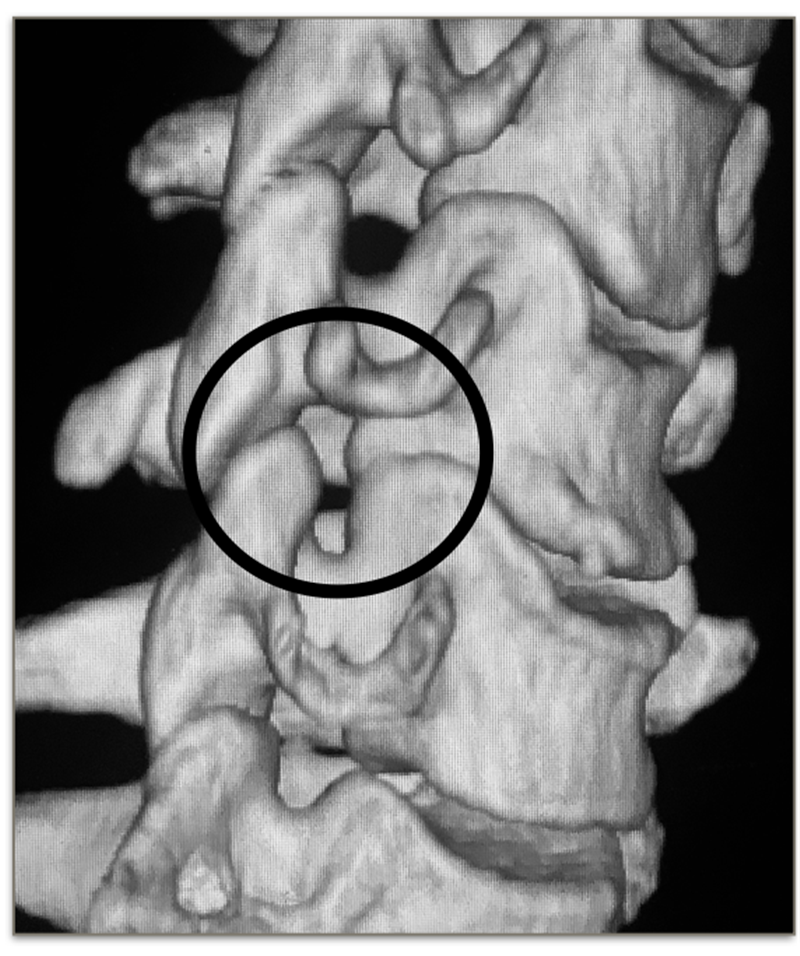

Orofinod等人发现,在成人颈椎中,原本存在于钩突与上位椎体间的疏松纤维组织、血管被纤维软骨及新生骨组织所代替。这一改变使得钩突被认为是随着年龄的增长而出现的一种退变现象。在颈椎退变过程中,由髓核脱水、椎间盘高度丢失等因素导致钩突与上一位椎体直接接触面积增大或承载压力变大,因而在钩突周围出现骨赘。

增生的钩椎关节